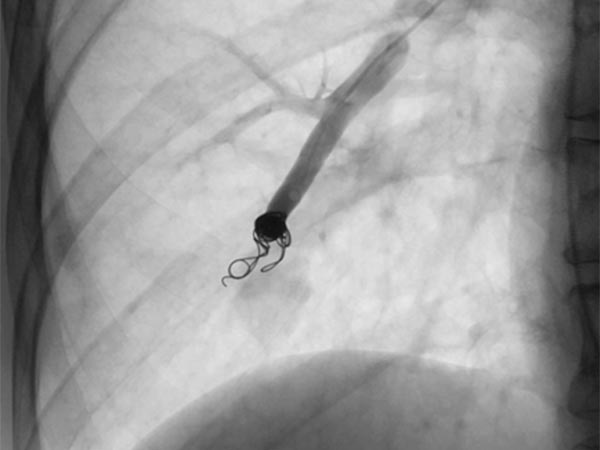

The feeding arteries are occluded with several coils. Parts of the coils are placed in the arterial feeding branch for secure anchoring (anchor technique). The pulmonary AVM is occluded. In the former aneurysm there is still some contrast medium stasis from a previous injection.

Completion DSA via the pulmonary trunk shows no more flow into the pulmonary AVMs.

Completion DSA via the pulmonary trunk in the parenchymal phase confirms complete occlusion of the pulmonary AVMs.